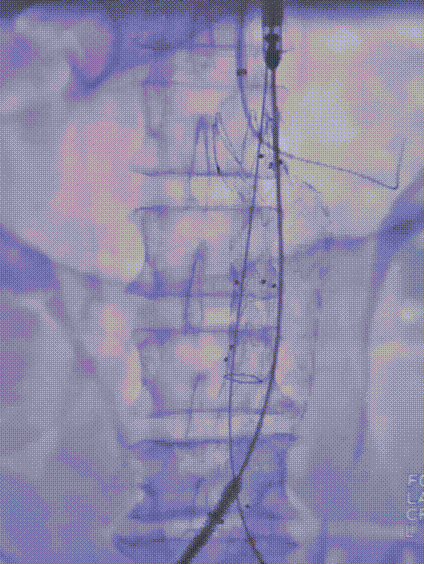

影响支架即时移位的因素

支架与血管壁之间充分的贴合和作用力是精准定位的关键。支架的选择、OVERSIZE(支架相对于瘤颈的放大比例)、释放技巧和瘤体形态等因素均会影响支架的即时移位。最终原因是瘤颈与支架之间的物理作用力不充分或不均衡。

瘤颈与支架的垂直作用力和水平摩擦力

垂直作用力主要由OVERSIZE决定,合适的OVERSIZE可以确保支架与瘤颈的良好贴合。

水平摩擦力则受瘤颈长度和OVERSIZE的影响,两者共同作用确保支架的精准定位。